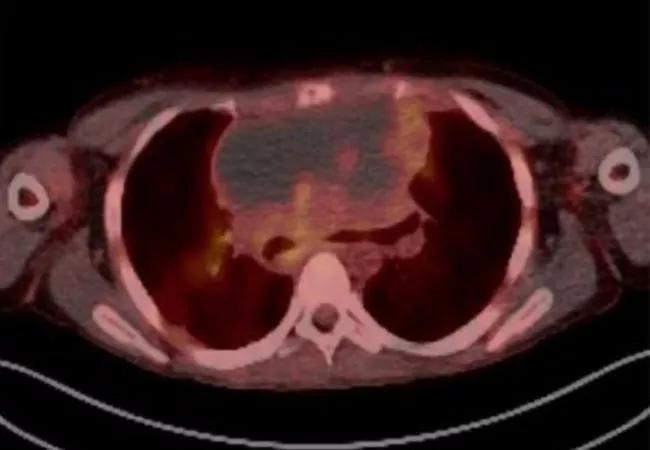

A, Initial bronchoscopic view of the very distal trachea with inability to see the main carina or main stem bronchi. B, Distal trachea metallic stent deployment showing mild improvement in airway patency but still with significant stenosis. C, Initial CT chest demonstrated an 18 × 12 × 16 cm anterior mediastinal mass. CT imaging also demonstrated a 3 cm right renal pole mass, and near complete effacement of the superior vena cava with extensive collateral formation (not shown).D, Bronchoscopic view of distal trachea on ED 12/HD 21 demonstrating mildly improved compression, but the anterior mediastinal mass invading through the trachea (arrow). The erosion remained essentially sealed throughout treatment as no pneumomediastinum developed. E, Positron emission tomography (PET) scan performed while on extracorporeal membrane oxygenation (ECMO) demonstrating a mostly necrotic tumor with mildly hypermetabolic ring surrounding the periphery. F, PET scan at the end of therapy demonstrating fluorodeoxyglucose (FDG) avidity in the periphery (Deauville 4). A transbronchial biopsy was obtained of an FDG avid portion of themass and demonstrated cellular debris and necrosis. Several subsequent PET scans continued to show mildly hypermetabolic areas, thought to be due to macrophages breaking down residual necrotic tumor; tumor dimensions continued to decrease on subsequent scans. G, Residualmass on CT scan at 9 months after the completion of final course of dose-adjusted etoposide, prednisone, vincristine, cyclophosphamide, doxorubicin, and rituximab (DA-EPOCH-R). H, Airway view of patient’s distal trachea and residual mass immediately after the completion of final cycle of chemotherapy. (I) and at 9 months post-therapy with re-epithelialization. Note: (a) anterior trachea; (b) posterior trachea.*

Extracorporeal membrane oxygenation (ECMO), delivered over the course of 40 days, proved to be a lifesaving intervention in an 18-year old man with primary mediastinal B-cell lymphoma invading into the trachea. While on ECMO, the patient successfully underwent fluorodeoxyglucose positron emission tomography (FDG-PET) imaging and treatment with radiation and chemotherapy, and eventually fully recovered. The case study, published in the May 2020 issue of Pediatric Blood & Cancer, established for the first time the utility of long-term ECMO in oncology.

Initiating ECMO under extreme circumstances